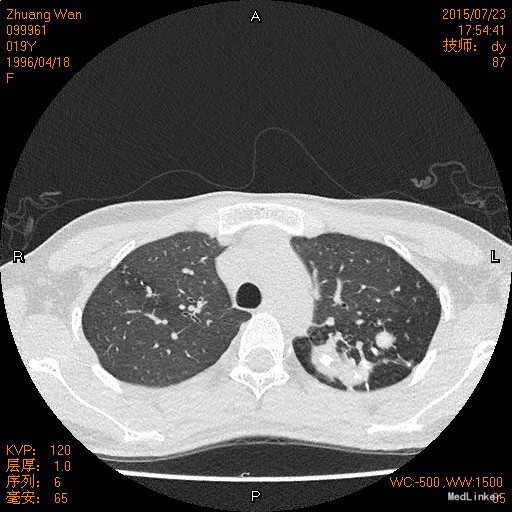

年轻女性患者,9月余前自觉呼吸时气管里发出声音,为持续性,查支气管镜检查确诊为左主支气管狭窄。先后曾于外院及我院共行球囊扩张5次,治疗后上述症状消失。现患者返院复查来我科。既往左上肺结核病史1年余,目前口服异福胶囊、乙胺丁醇治疗。

查体:双侧胸廓不对称,未见明显畸形,左肺上叶呼吸音弱。 辅查: 胸部CT:双肺上叶结节影,考虑结核可能性较大;左侧支气管狭窄。

诊断:左主支气管狭窄 双侧肺结核 治疗: 排除禁忌症后,在呼吸内镜室行支气管镜下气囊扩张术,嘱术后坚持规律服用抗结核药物,不可自行停药,定期复查血常规、血沉、肝肾功能,至当地结核病防治所随诊。